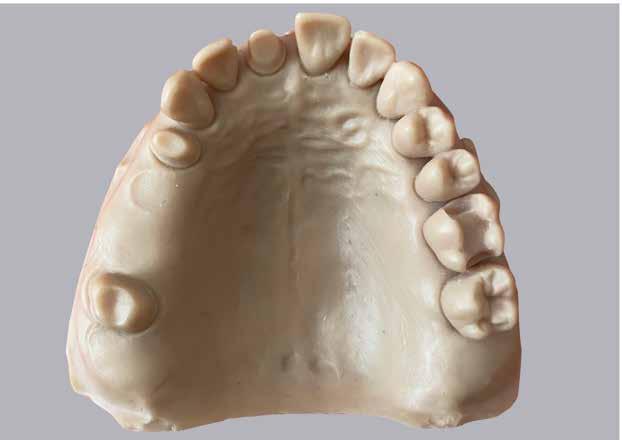

Az esztétikus zónában a felső kismetszők implantátumokkal történő pótlása az egyik legnagyobb kihívás. Ha a kiindulási állapotban még szájban van a reménytelen prognózisú fog, bizonyos esetekben azonnali implantáció és azonnali provizórium készítéssel könnyen elérhető ideális esztétikum, viszont a csírahiányos esetekben csakis késői implantációs protokoll jöhet szóba, melyet általában ki kell egészítsünk valamilyen szövetpótlással. Meglátásom szerint a fogorvosok néha tanácstalanok, hogy ilyen esetekben hogyan kell eljárni, ezért esett erre a témára a választásom.

Legyen kedves, mondja el röviden szakmai életútjának és tudományos munkásságának legfontosabb állomásait! 2008-ban végeztem summa cum laude minősítéssel a Semmelweis Egyetem Fogorvostudományi Karán, majd felvételt nyertem az egyetem Parodontológiai Klinikájára szakirányú továbbképzésre. 2013-ban parodontológiából, majd 2019ben az újonnan alapult orális implantológiából szereztem szakvizsgát. Elsőként publikáltam hazai tudományos folyóiratban metaanalízist is tartalmazó szisztematikus áttekintést, mellyel 2017-ben a Körmöczi-díj első helyezettje lettem. Tudományos érdeklődésem és egyben klinikai vizsgálataim fókusza a parodontális regeneráció és az ortodonciai fogmozgatás kapcsolata. 2020-ban elnyertem az IADR Karring–Nyman SUNSTAR Guidor-díját a klinikai vizsgálatom eredményei után, mely eredmények egyben PhD disszertációm alapját is képezték. A doktori fokozatot 2021-ben szereztem meg, azóta adjunktusi beosztásban, részállásban dolgozom a Semmelweis Egyetem Parodontológiai Klinikáján. A tanszéken nemcsak a graduális, hanem a posztgraduális oktatásban is részt vállalok Windisch professzor úr irányítása alatt.